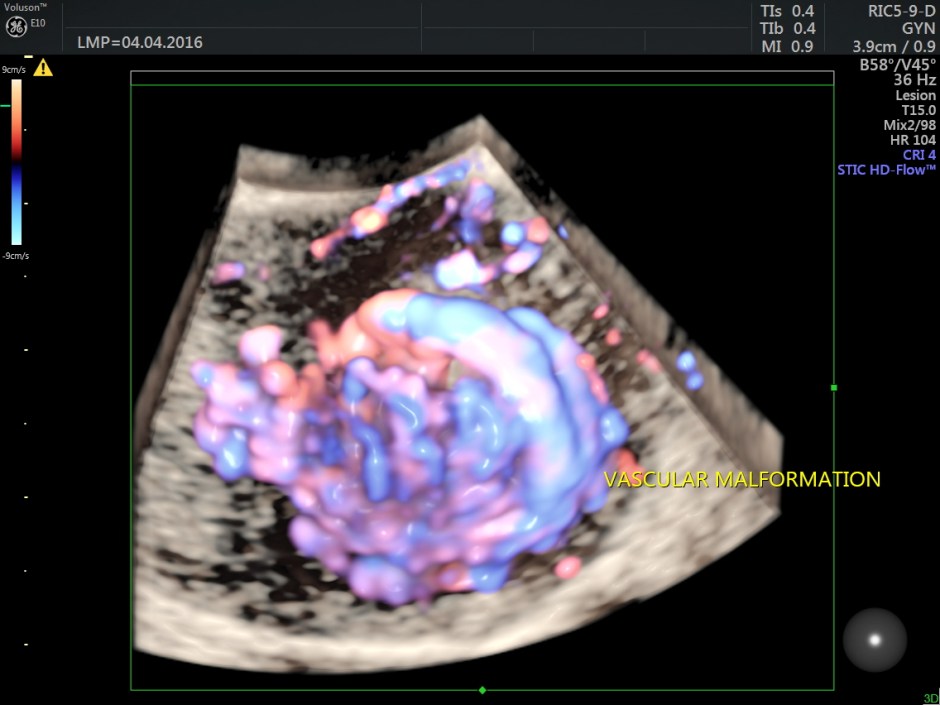

Power Doppler reconstruction images of trans-abdominal scan are given below

The following are the different sections of the Power Doppler reconstruction images of the trans-vaginal scan.

The following are the reconstructed 3D Power Doppler images.

For comparison a 2 d image is given below.

The ultrasound diagnosis was a vascular malformation in the uterus .She was referred to an interventional radiologist,who did a CECT the next day.